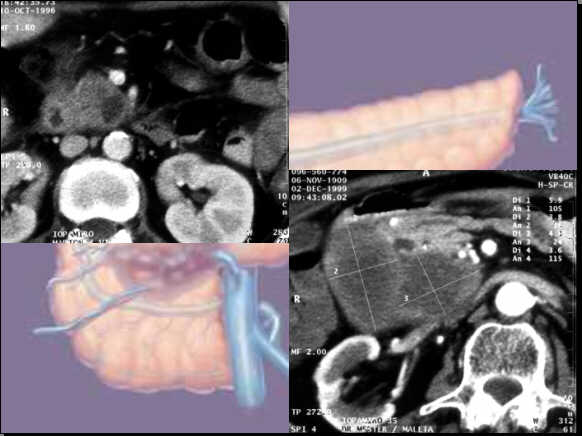

Generally the differentiation is problematic:

Cystic

lesions in the uncinate process: Pancreatic pseudocyst.

Enlarged

pancreatic head with intraparechymal conglomerate of

cysts, well demarcated with hypervascularised septas: Macrocystic adenoma.